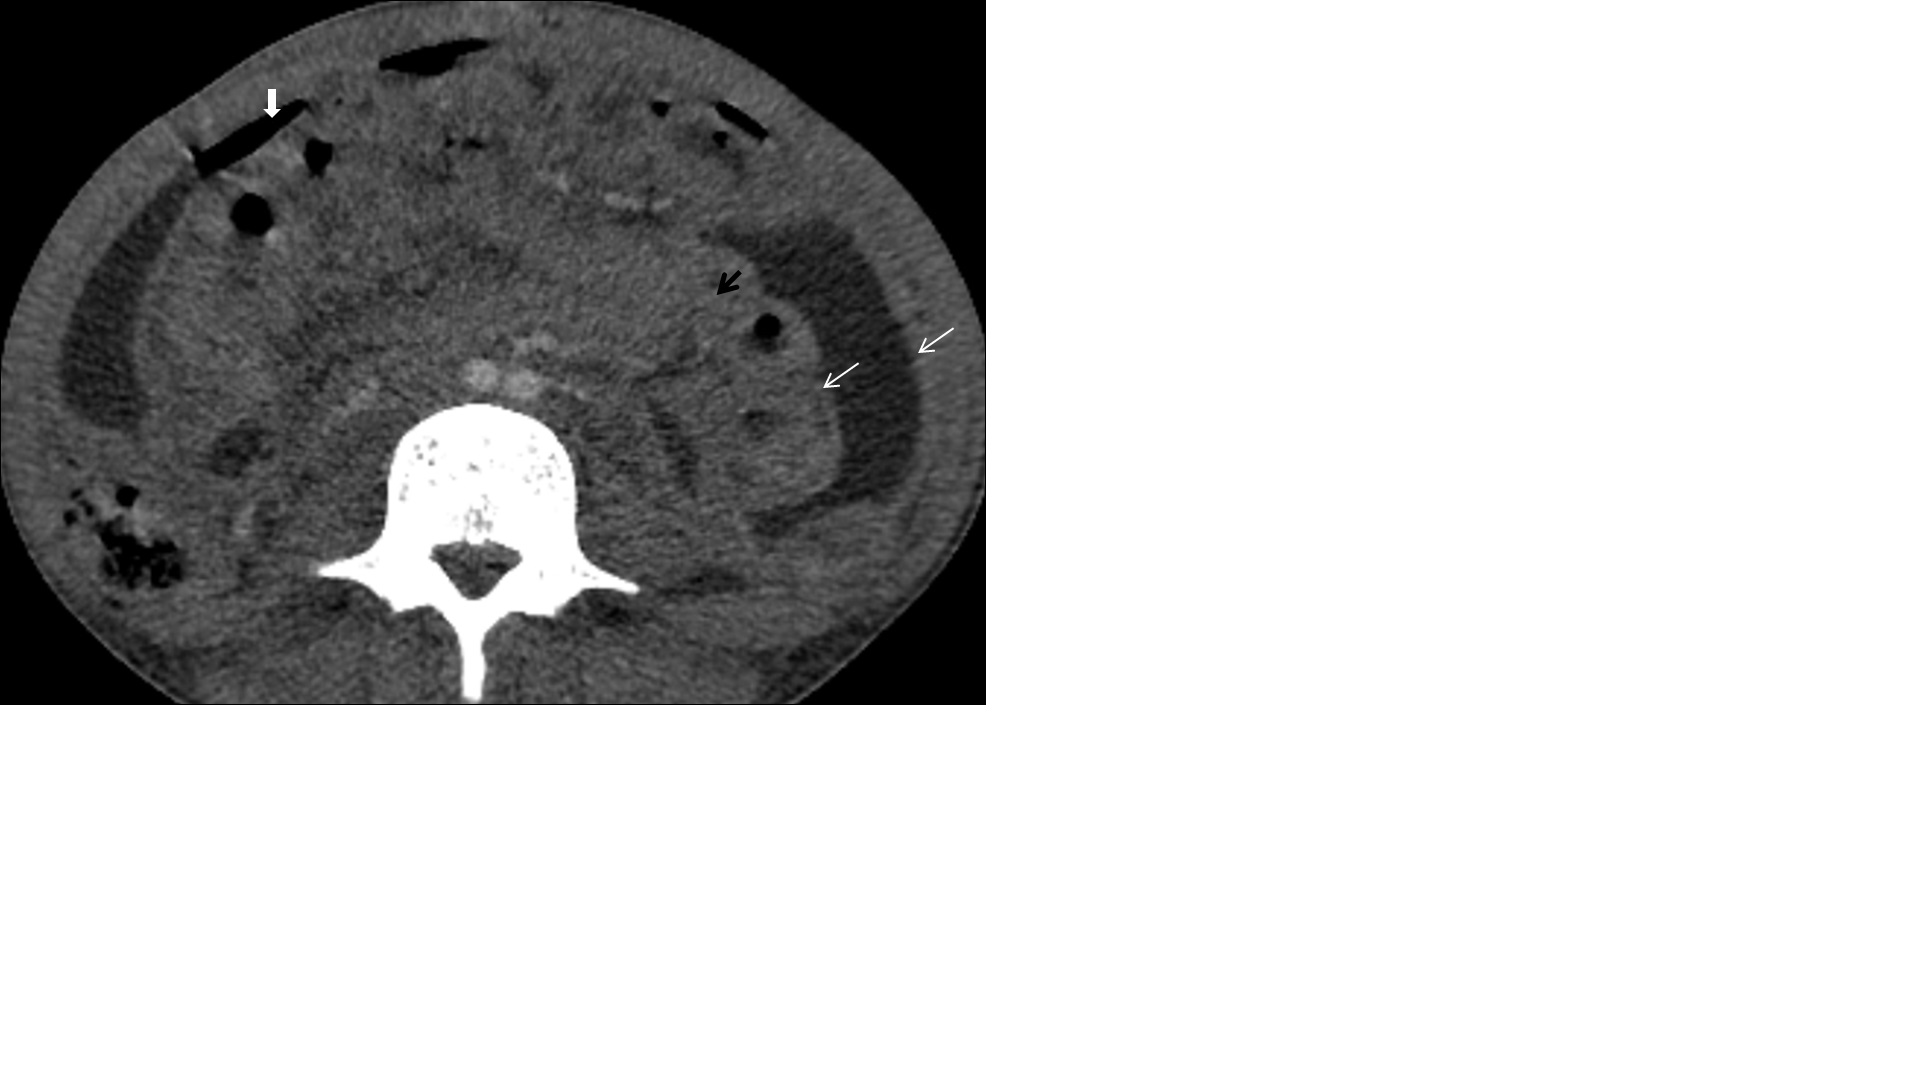

Tubercular lymphadenitis

Lymphadenopathy is the commonest finding associated with abdominal tuberculosis. A wide range of patterns can be seen, including an increase in the number of lymph nodes to large nodal masses. The commonly involved lymph nodes groups are omental, mesenteric, celiac, portahepatis and peripancreatic. The conglomerated pattern of lymph nodes is commonly seen in abdominal tuberculosis. In contrast, CT features of involved lymph nodes may vary from peripherally enhancing lymph nodes with low-density centres (signifies caseous necrosis) to homogeneous/heterogeneous enhancement. Lymph nodes calcification is also seen in chronic tubercular infection (Figure 1A,1B). The necrotic lymph nodes are not pathognomic for tuberculosis as they can also be seen in metastasis, lymphoma or Whipple’s disease [4].

Figure 1: (A) A 30 years old male patient came with a complaint of vague pain abdomen, low-grade fever and a history of significant weight loss in the recent past. On physical examination, there was diffuse pain in the abdomen without any organomegaly. Postcontrast computed tomography image from a venous phase in the axial plane illustrates multiple, conglomerated, peripherally enhancing para-aortic (white arrow) & mesenteric (black arrow) lymph nodes with central necrosis. (B) In another 60 years old male patient with similar complaints, a post-contrast computed tomography image from a venous phase in the axial plane shows heterogeneously enhancing, enlarged, and conglomerated lymph node masses with internal low attenuating areas and punctate calcification (thick white arrow) in the left para-aortic region. Both these patients were diagnosed with TB on CT guided lymph node FNAC and anti-tubercular therapy was started. Patients are now symptomatically better and kept on follow up.